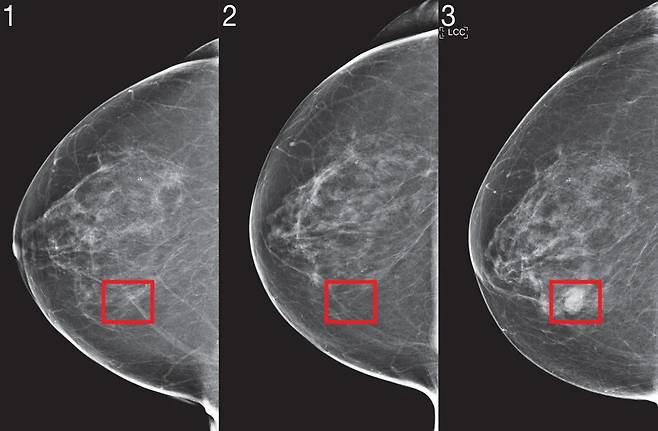

매사추세츠공과대학(MIT) 컴퓨터과학 및 인공지능 연구소와 자밀클리닉 연구팀은 유방암 발병 위험을 예측하는 인공지능 시스템을 만들었다. ‘미라이’란 이름의 이 알고리즘은 매사추세츠 종합병원의 20만건 넘는 유방암 데이터를 학습해 5년 안에 유방암에 걸릴 확률을 진단해낸다. 흑인과 백인 여성 모두에게서 똑같은 정확도를 보여줬고, 촬영 시기나 추적 관찰 기간이 다른 환자들에게서도 일관된 예측 결과를 내놓았다. 이 유방촬영술을 이용하면 다양한 임상 환경에 놓인 환자들이 불필요한 검진을 줄이고 유방암 발병 가능성을 조기에 진단하고 예방할 수 있다.